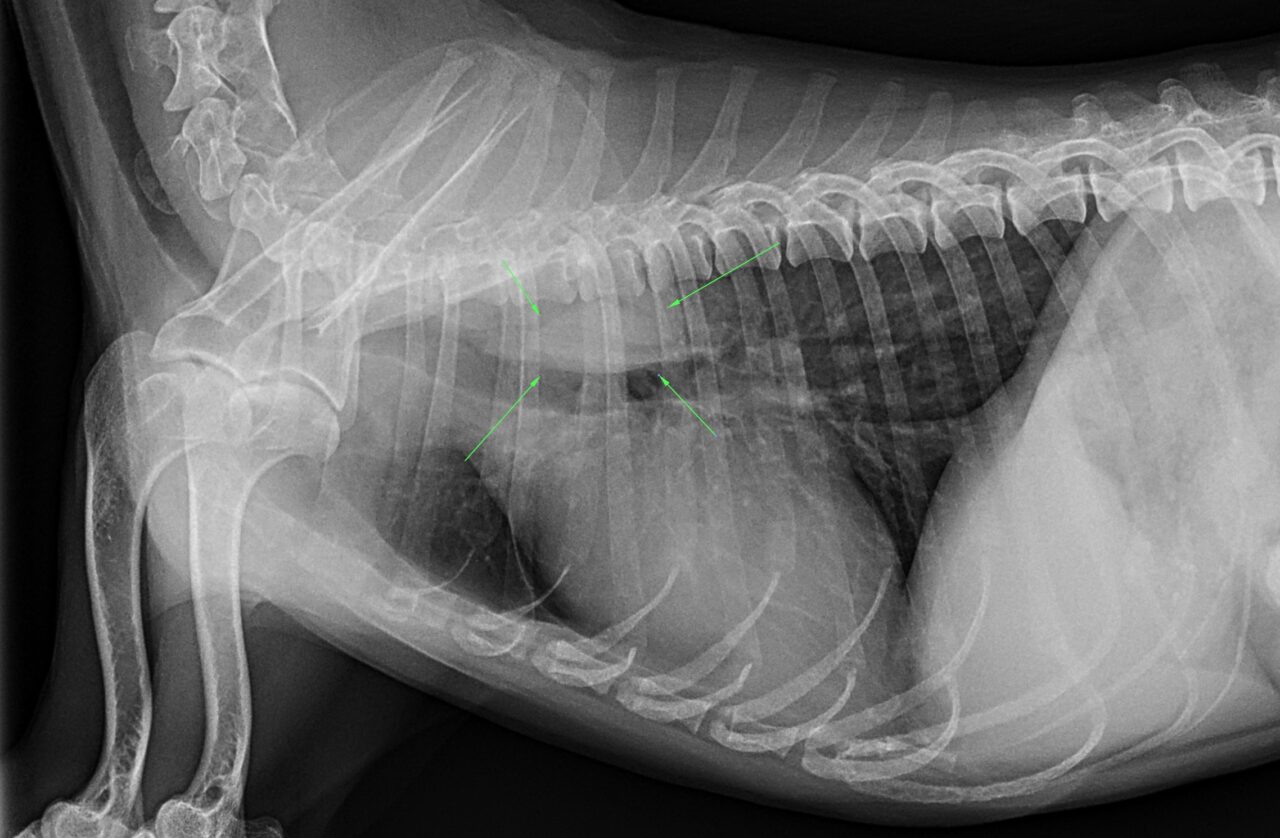

食道内異物(ジャーキー)

X線検査で食道内の異物を疑う所見が得られ、ジャーキーが閉塞していると判断して内視鏡摘出を行いました。